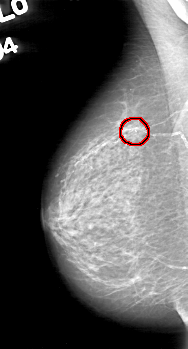

D_4044_1.RIGHT_MLO

RIGHT_MLO LINES 5221 PIXELS_PER_LINE 2806 BITS_PER_PIXEL 12 RESOLUTION 43.5 OVERLAY

FILE: D_4044_1.RIGHT_MLO.OVERLAY

TOTAL_ABNORMALITIES 1

ABNORMALITY 1

LESION_TYPE CALCIFICATION TYPE COARSE DISTRIBUTION CLUSTERED

ASSESSMENT 0

SUBTLETY 5

PATHOLOGY BENIGN

TOTAL_OUTLINES 1